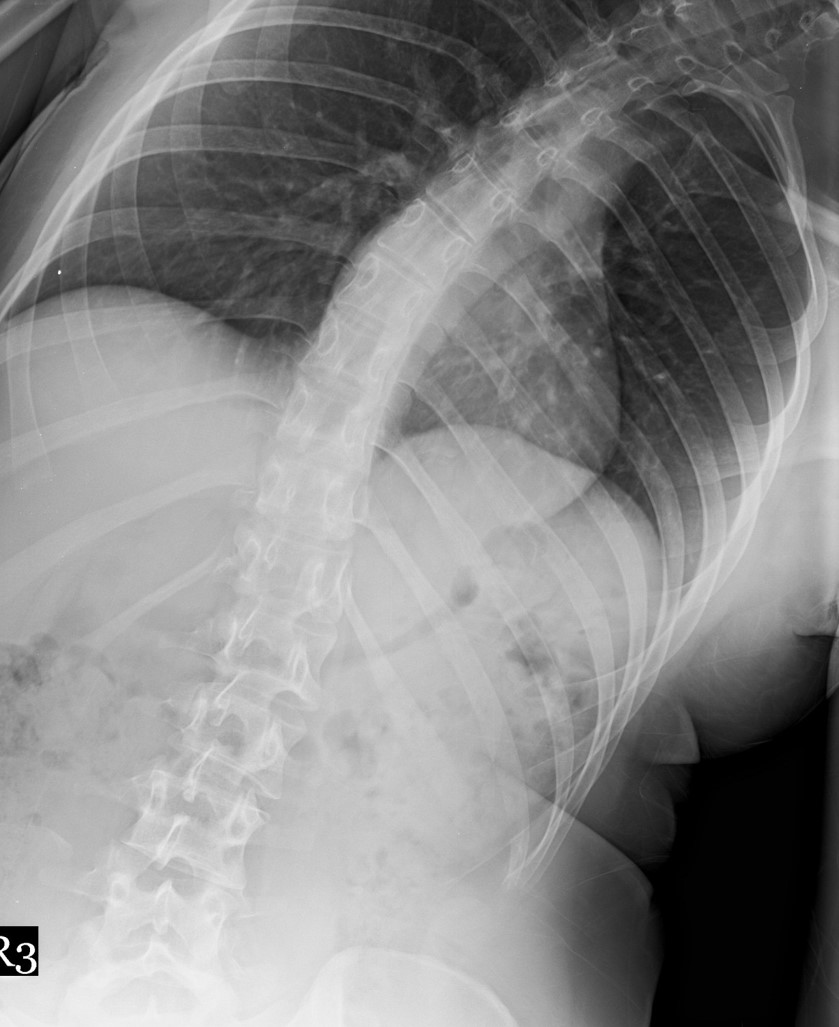

20 Yaşında Kadın Hasta

Boy: 171.3cm.

Kilo: 66kg

Rib hump lomber 10 derece

Ameliyat Öncesi